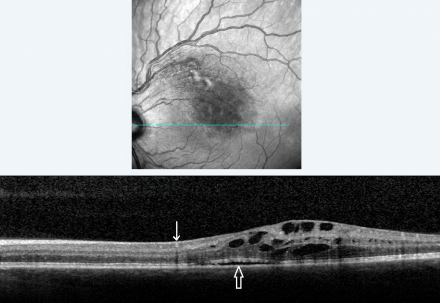

Characteristic findings of BRVO on OCT are cystoid macular edema, intraretinal hyperreflectivity from hemorrhages, shadowing from edema and hemorrhages, and occasionally subretinal fluid (Figure 4). Unlike FA, OCT images are minimally affected by intraretinal hemorrhages. The third high reflectance band corresponds to the junction between inner segments (IS) and outer segments (OS) of photoreceptors. This band (also called the ellipsoid zone) has prognostic significance for visual acuity. Disruption or absence of the ellipsoid zone after macular edema resolution is an indication of photoreceptor cell death or disarrangement and correlates with poor visual acuity (Figure 5).[30]